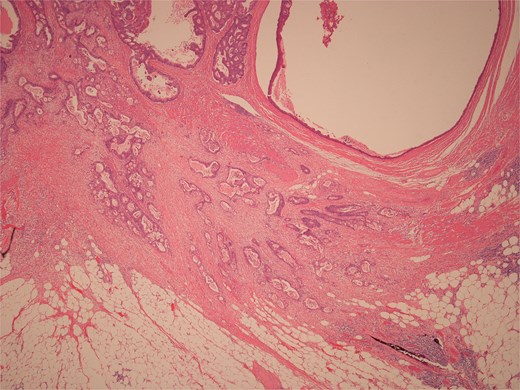

Histopathological examination of surgical specimens revealed three distinct neoplasms: (i) invasive colonic adenocarcinoma (Figs 4 and 5), (ii) jejunal NET (Figs 6 and 7), and (iii) small-lymphocytic lymphoma (Figs 8 and 9). Morphological assessment supported by immunohistochemical profiling confirmed each represented an independent primary, with no evidence of a shared clonal origin. The findings were subsequently reviewed at the Multidisciplinary Meeting alongside Oncology and Haematology specialists, and adjuvant single-agent chemotherapy was initiated, with planned surveillance of the indolent lymphoma.

Low power view of colonic adenocarcinoma invading muscularis propria and pericolonic fat.

High power view of colonic adenocarcinoma showing complex glandular structures lined by epithelial cells with high grade atypia, and lumina containing necrotic debris, invading beyond the mucosa.